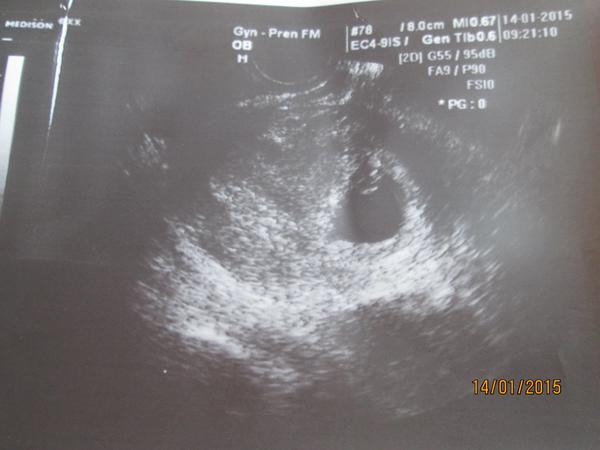

Dobré dopoledne holky moje. Tak jsem doma z kontroly.Hlásím,že podle slov doktorky jsme naprosto ukázkoví,učebnicoví 🙂 Těhu odpovídá opravdu 5 + 6 tt. Mimisek má 4 mm a paní doktorka už zaznamenala i srdeční akci 🙂 Takže vše v naprostém pořádku . Přikládám fotečku i když teda na ni ještě není moc k vidění 🙂 .Příští KO máme za 14 dní 28.1 .

Mimčo na té fotce vypadá jako malý netopýr visící ze stropu 😀 😀 😀 😀